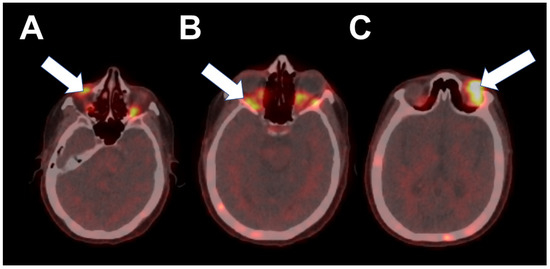

2. Case 1